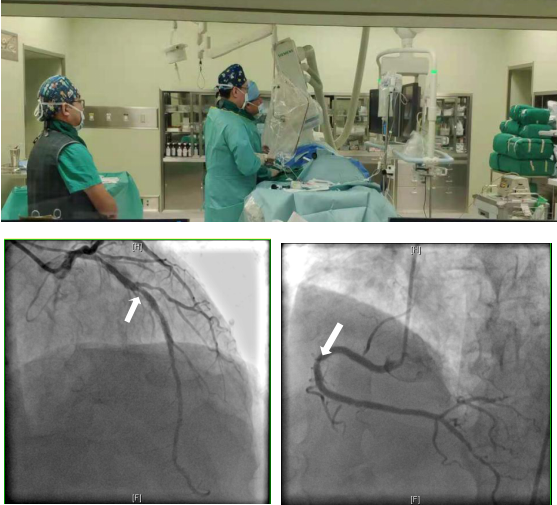

FFR检查是将带有压力传感器的导丝送到冠脉狭窄病变的远端,通过测量狭窄病变远端与近端处压力比值,评估血管狭窄是否引起心肌缺血。FFR检查可提高诊断的准确性,但存在几个不利因素:一是需要使用价格昂贵的压力导丝;二是导丝要被送至冠脉血管内,属于有创操作;三是检查过程中还需使用血管扩张药物,术中可能会出现低血压等并发症;最后是检查耗时,需要30-40分钟。

鉴于以上情况,北京清华长庚医院引进了最新的定量血流分数检查(以下简称QFR),该检查依靠冠脉造影三维重建技术和血液动力学系统,可实现精确分析狭窄冠脉血管的功能学指标,与FFR相比,是无创评估冠状动脉生理功能指标的“新标准”。同时,QFR不使用压力导丝及扩血管药物,更不需要进入体内,3-5分钟即可完成检查,检查费用相对低廉,与FFR准确性相当,便利冠心病患者接受更精准的治疗,避免更多的支架植入。目前,北京清华长庚医院已经掌握该项技术,并广泛应用在冠心病的诊断与治疗过程中,到现在已经使用OFR技术治疗100多例患者。